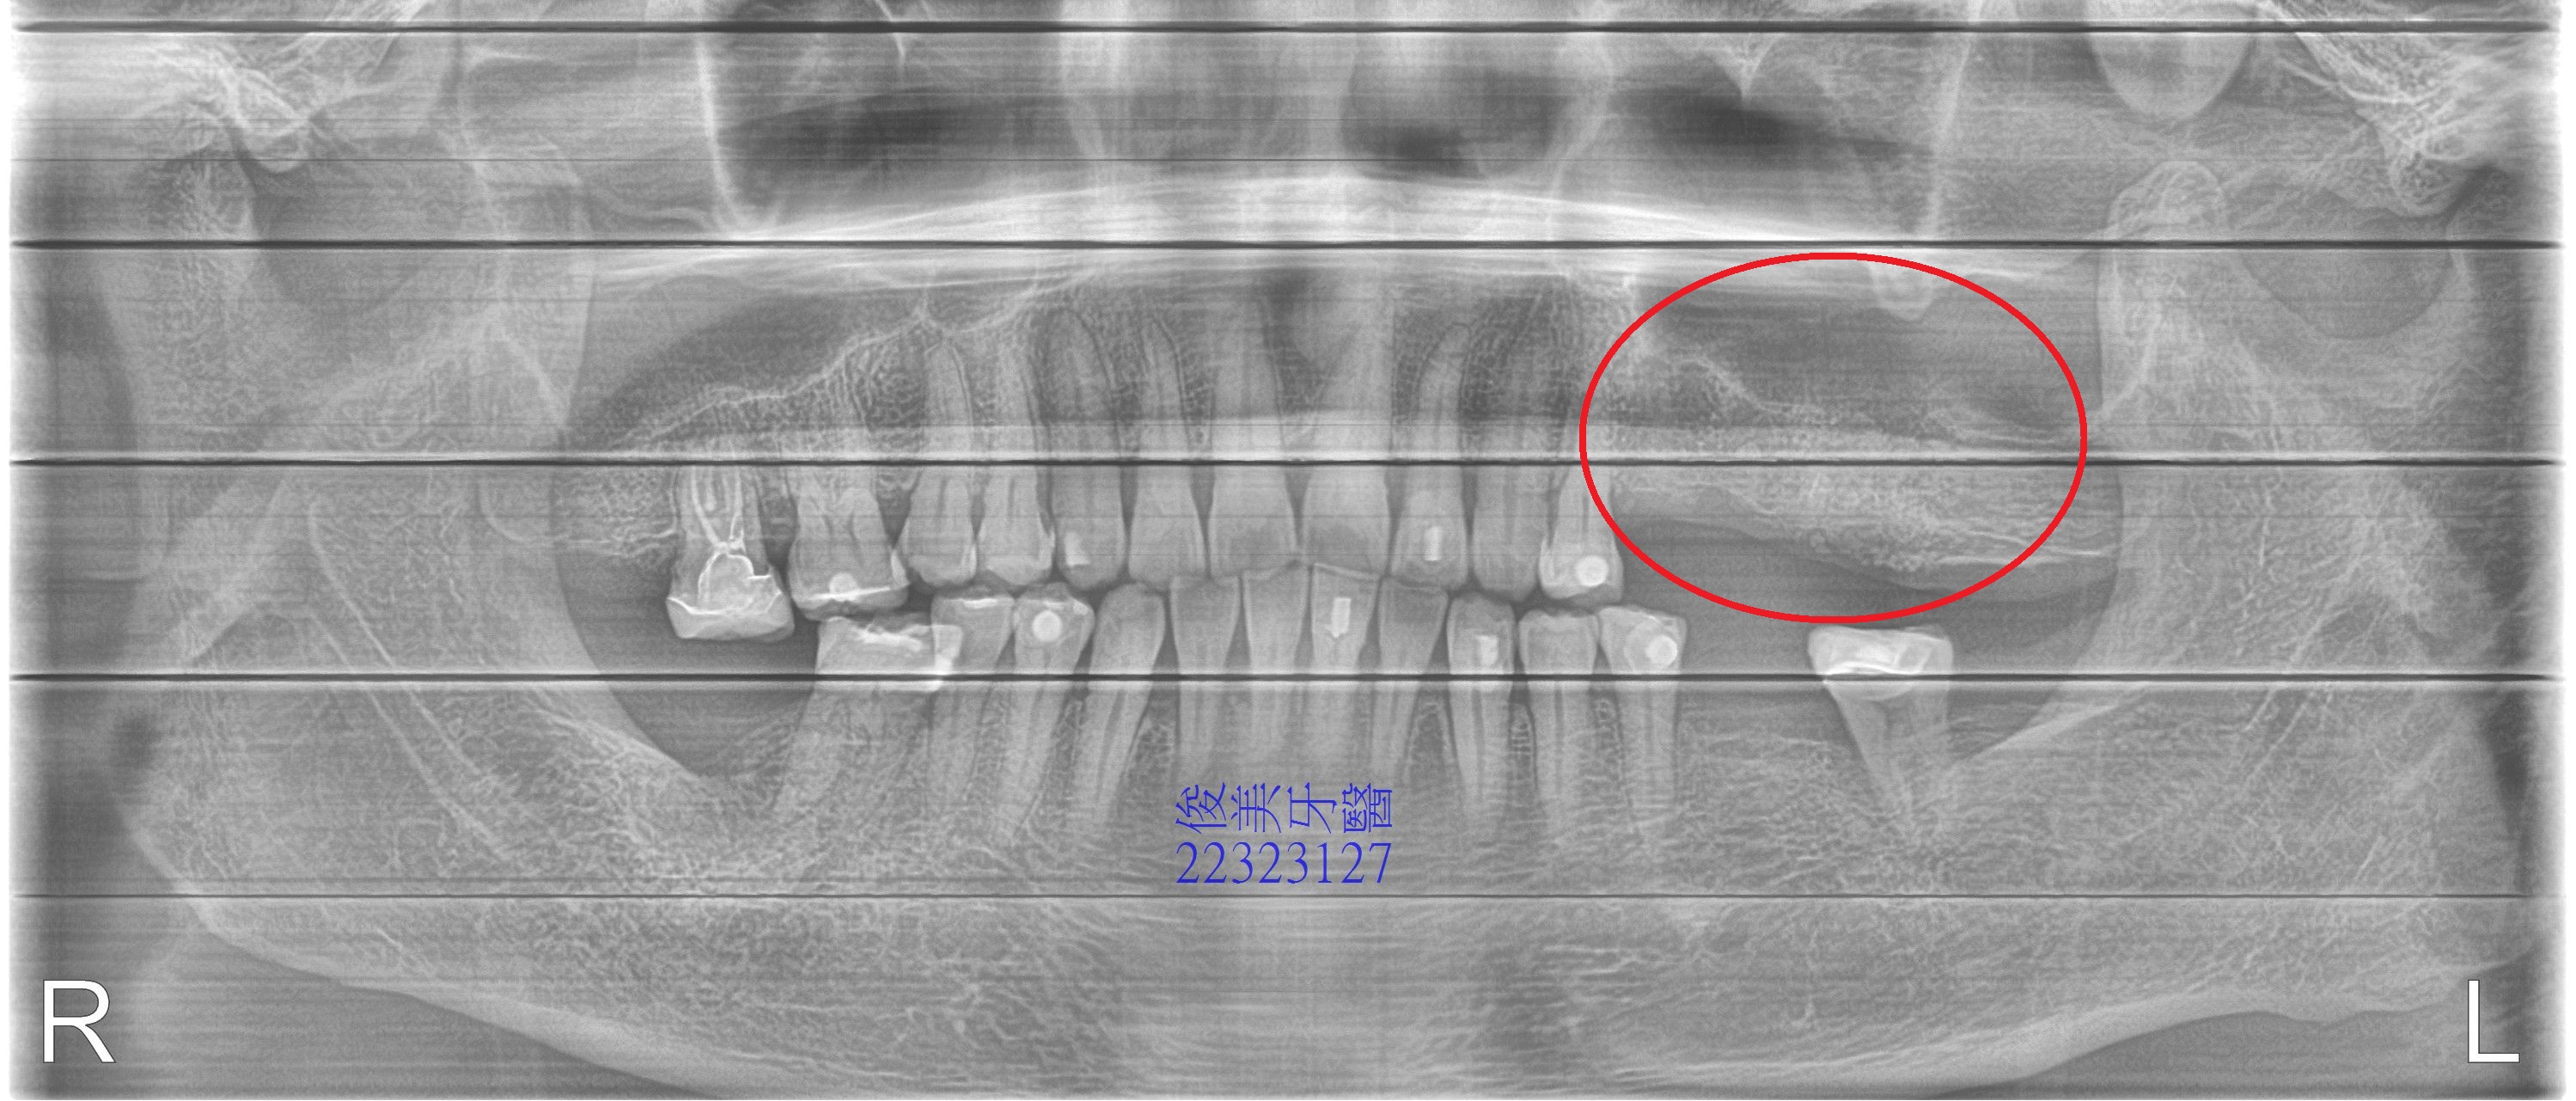

醫師檢查後,建議患者做全口重建,因咬合嚴重于擾,且患者右邊咬合很差,因此長期使用左邊咀嚼,加上患者咬力大,左邊上排牙齒皆抽過神經,長期刺激下,使得根尖產生病變及骨頭破壞,因此鼻竇持續有感染的現象,於拔牙後,將患處組織刮除及清洗,術後患者就再也沒有說有症狀了。

5個多月,患者原先骨頭破壞處,也修復了許多。